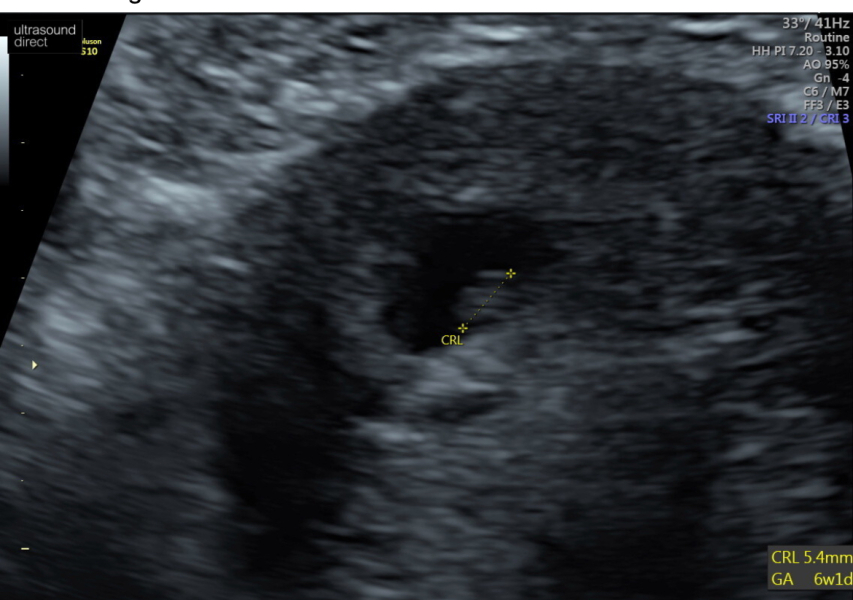

magicalmama · 27/04/2024 18:25

It was 6w+2days and the heartbeat was just 114. I thought this is low but they said it's only just started beating so this is healthy. They said it is too early to date it though (even though I am very sure of my dates) and will do that a bit better at the 8 week scan.

I think that's when I read the heard should be beating and also once they can measure a crown to rump length of 5mm.

Had my scan today! Said I must of ovulated later then I thought, well I wasn’t sure when I had am a little confused tho as they put me at 6weeks 1 day and I got my clear blue 3+ on the 15th ? I’m confused but trying to stay positive as I saw heart beat 🖤 due date of 21/12/24 xx